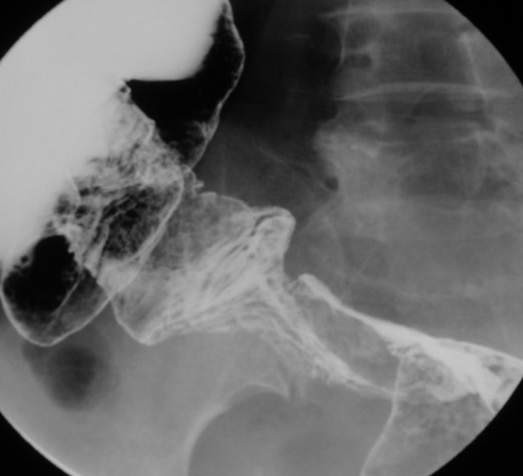

67岁女性,腹痛、腹胀半月余。查:右侧腹部有触痛,可触及肿物。

支持升结肠肿瘤性病变。

常规考虑---结肠癌,不排除诱发肠套叠了。

支持升结肠癌。

支持考虑升结肠癌。

谢谢大家讨论。与x6045完全不同。本例手术结果为右侧结肠旁沟及盆腔多发脓肿。术后病人恢复良好,现已出院。

感谢楼主反馈结果!造影见果核征,首先考虑肿瘤,即使误诊也应该这样考虑。